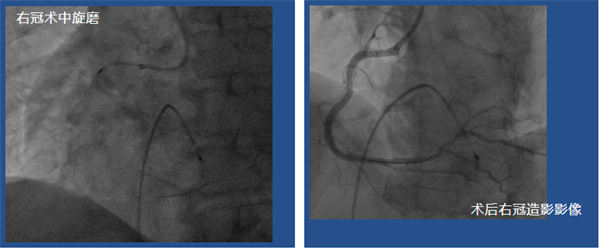

鄭廣生團(tuán)隊(duì)經(jīng)過對(duì)手術(shù)難點(diǎn)的分析提出了相應(yīng)的手術(shù)策略順利為患者實(shí)施了手術(shù):患者73歲高齡,冠脈多支嚴(yán)重鈣化狹窄,存在左主干病變,右冠重度鈣化,需要主動(dòng)行冠脈旋磨治療,經(jīng)充分處理右冠病變后,于右冠植入支架3枚。術(shù)后患者的胸悶、氣短癥狀明顯緩解,已于近日康復(fù)出院。

術(shù)后右冠造影影像